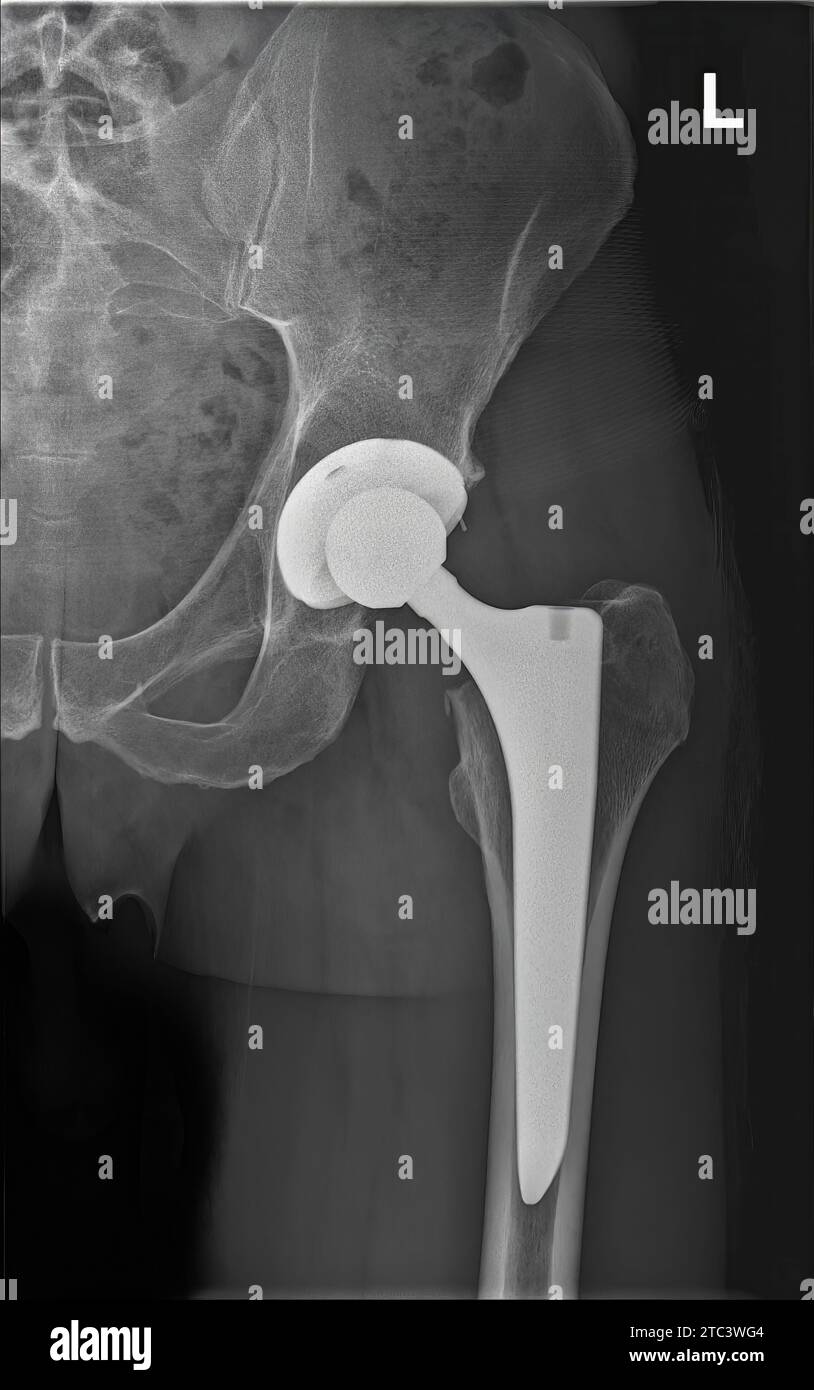

Xray photo of left hip prosthesis of man. Total hip replacement. 6 Is Total Hip Replacement Dangerous A hip replacement is a common and safe procedure. Definition and causes hip replacement surgery, often considered a lifesaver for those suffering from severe hip pain and mobility issues, typically. Blood clots in the leg veins (deep vein thrombosis) and blood clots on. Also called total hip arthroplasty, hip replacement surgery might be an option if hip pain interferes with. Is Total Hip Replacement Dangerous.